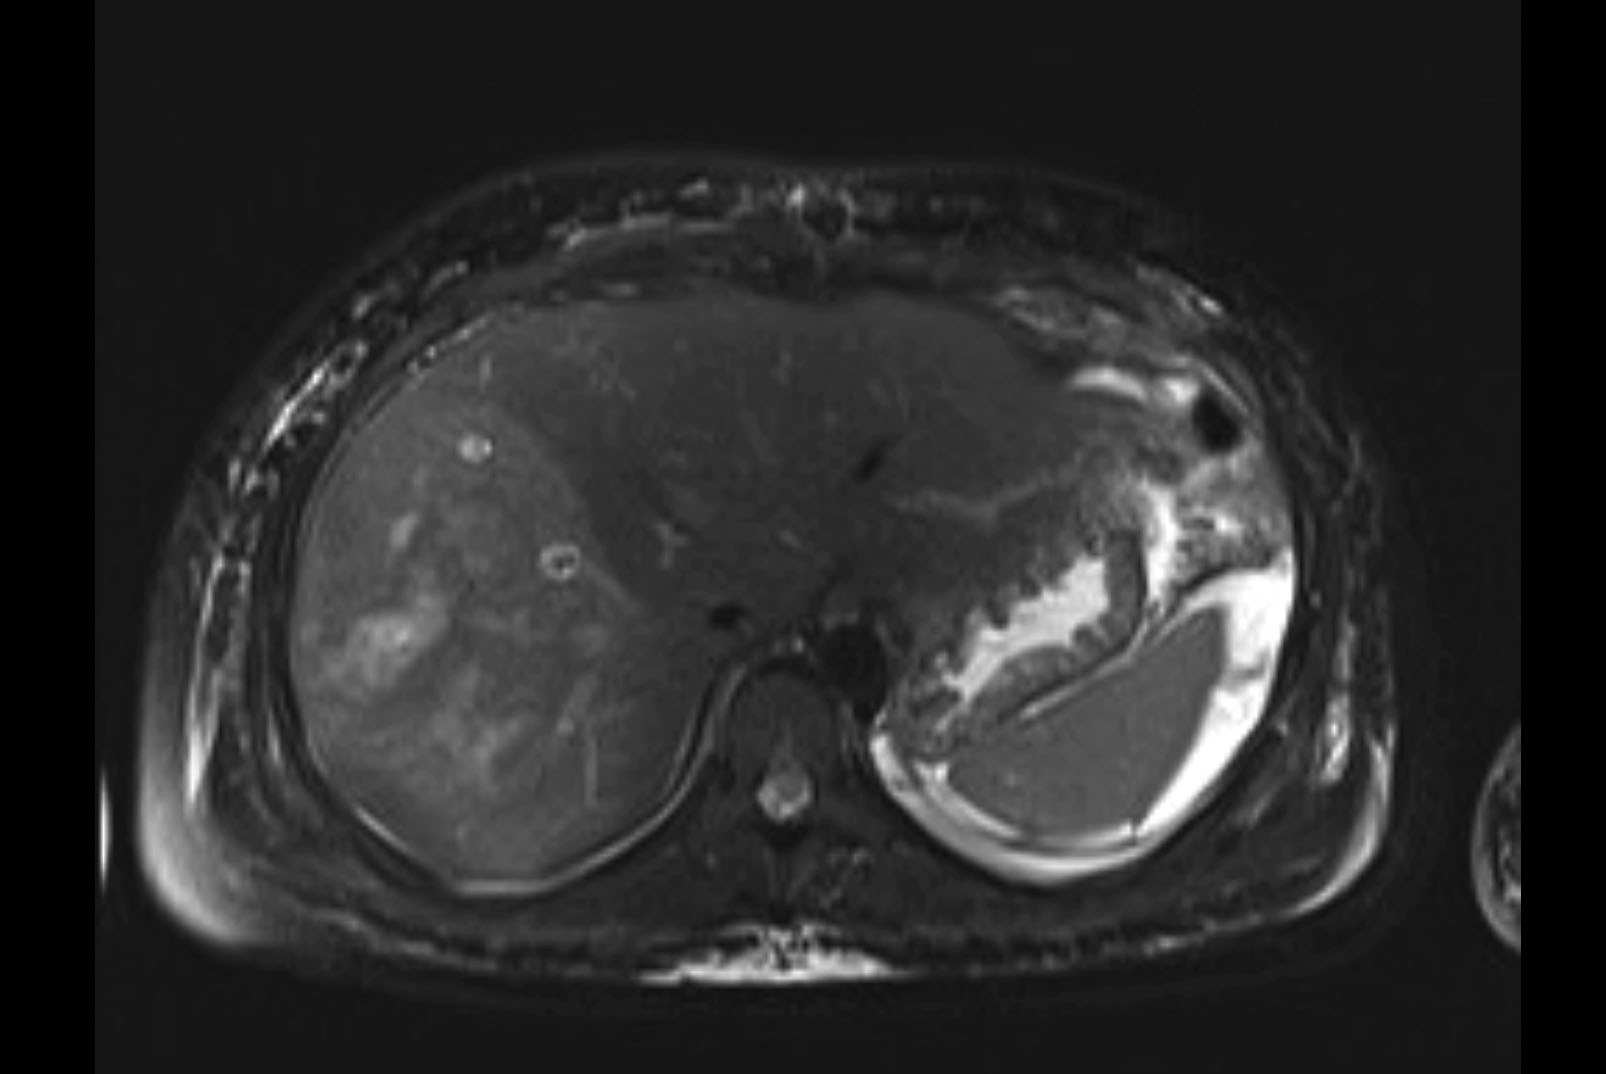

Imaging Analysis

Look through the patient's CT scan to identify any areas of concern for the necessary procedure.

MRI T1

MRI T2

Based on initial findings, which issue(s) would you be most concerned about?